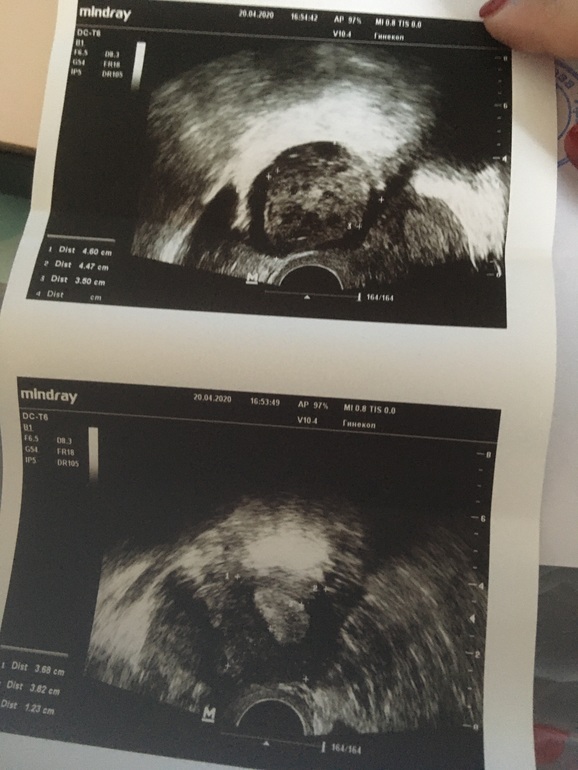

У меня всегда при б.была киста желтого тела.Это норма,ничего страшного.И эндометрий очень хоооший.Желаю //

Киста жёлтого тела это абсолютно нормально!!!это бывает у всех и по много раз за жизнь женщины!

Киста жёлтого тела, лютеиновая киста - разновидность кисты яичника, формирующаяся после овуляции в результате действия гормона гипофиза ЛГ. Относится к рамолиционным кистам. Формирование кисты жёлтого тела начинается сразу после овуляции

Киста ЖТ считается вариантом нормы, это значит, что овуляция была. Если Б не наступит, то она просто уйдет с месячными.